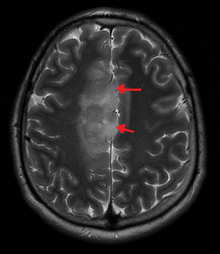

An X-ray computed tomography (CT) or magnetic resonance imaging (MRI) scan is necessary to characterize the anatomy of this tumor as to size, location, and its heter/homogeneity. However, final diagnosis of this tumor, like most tumors, relies on histopathologic examination (biopsy examination).